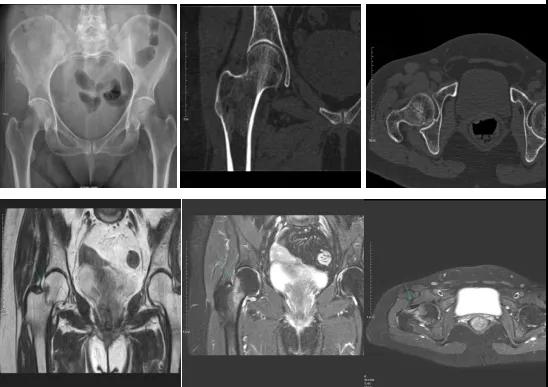

DR示:右側(cè)股骨頸未見明顯骨折征象。CT右側(cè)股骨頸骨質(zhì)密度不均?;颊唧w征明顯,為明確診斷,行MRI檢查。MRI示:右側(cè)股骨頸T1WI呈低信號(hào),脂肪抑制序列呈高信號(hào);提示右側(cè)股骨頸隱匿性骨折。